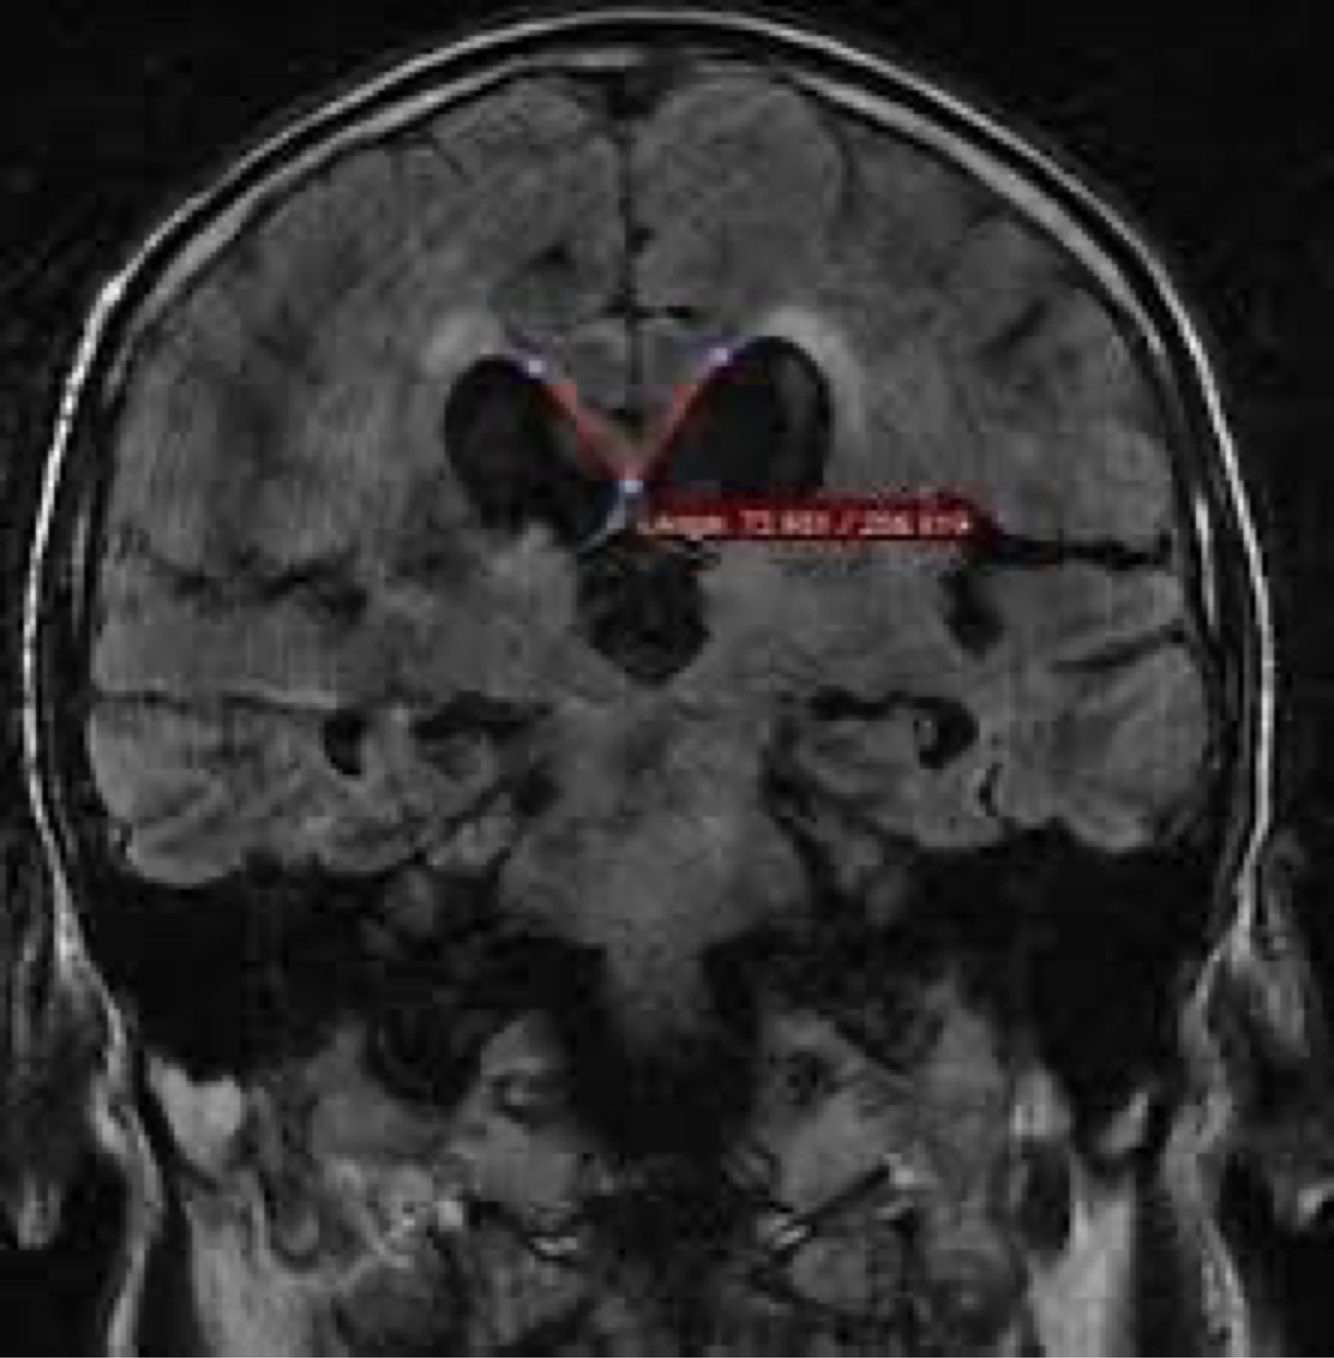

In iNPH what you gonna see in sagital view ct ?

A

corpus callosum angle

The callosal angle has been proposed as a useful marker of patients with idiopathic normal pressure hydrocephalus (iNPH), helpful in distinguishing these patients from those with ex-vacuo ventriculomegaly (see hydrocephalus versus atrophy).

It should be noted that there is nothing magical about this measurement, but rather it is merely a quantifiable measurement of the morphology of iNPH characterized by enlarged widening of the Sylvian fissures and cisterns with crowding of the gyri at the vertex.

Measurement

Ideally, the angle should be measured on a coronal image perpendicular to the anterior commissure - posterior commissure (AC-PC) plane at the level of the posterior commissure 1,2.

Interpretation

In general patients with iNPH have smaller angles than those with ventriculomegaly from atrophy or normal controls.

A normal value is typically between 100-120°. In patients with iNPH that value is lower, between 50-80° 2.